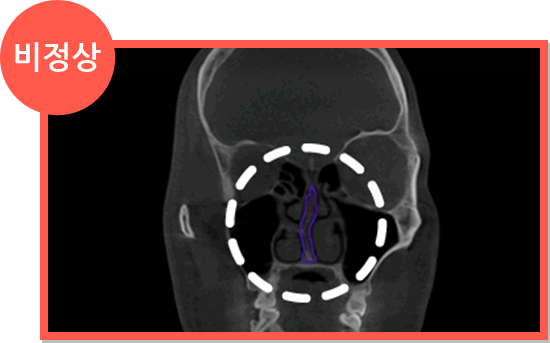

• 비중격만곡증에 의한 비염

비중격 연골이 휘어서 생긴 비염은 휘어진 비중격 연골을 교정하면서 비염 수술을 같이 해야 합니다.

비염 CT 정상 소견 비염 CT 비정상 소견